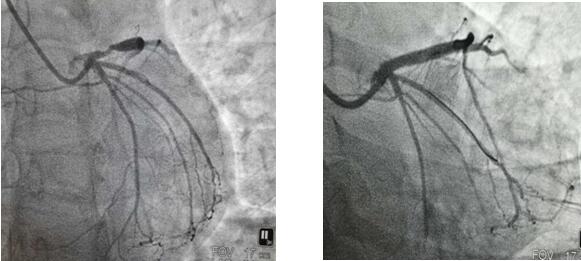

4月22日上午,患者王女士因“反復(fù)胸痛、胸悶半年”就診我院,行冠脈造影提示LAD段嚴重狹窄,經(jīng)全面評估患者病情,充分結(jié)合患者及家屬意愿后,今日上午為31歲的王女士成功植入生物可吸收支架一枚,手術(shù)過程順利,術(shù)后效果滿意。

支架植入前 支架植入后